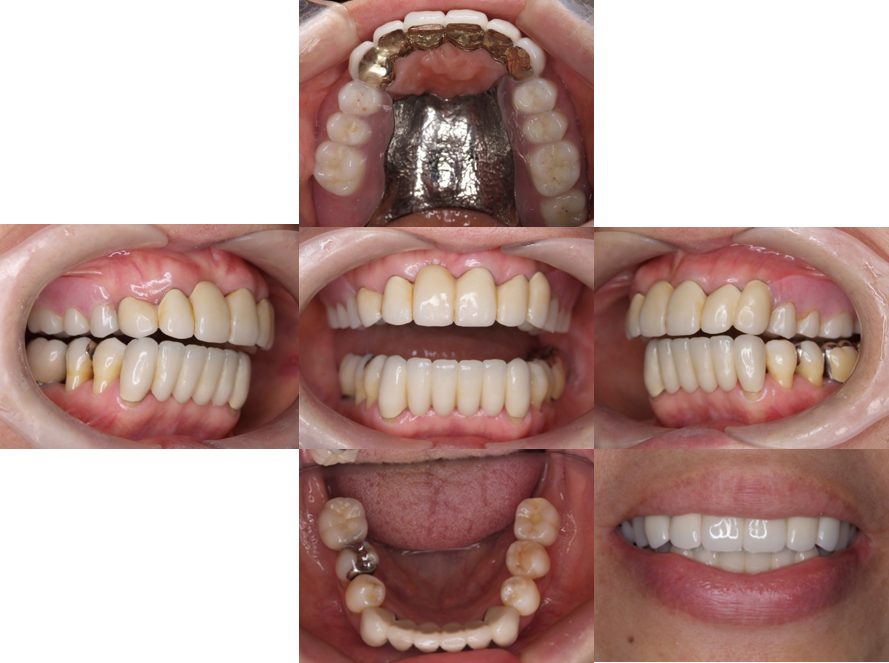

外科矯正治療・インプラント治療・セラミック治療の症例紹介(三隅歯科クリニック)

三隅 賢祐(三隅歯科クリニック)

症例詳細

| 主訴 | 50代男性 右上の歯と歯茎が痛い。どこで噛んでいいのか分からないので夜も眠れない |

| 治療内容 | 外科矯正治療・インプラント治療・セラミック治療を行いました。 |

| 治療費 | 4,500,000円(税込み) |

| 治療期間 | 4年(矯正治療期間 3年) |

| 治療回数 | 60回 |

| 想定されたリスク | 顎骨の変形があったので、全身麻酔下による外科処置が必要になり、身体的、精神的負担が増す可能性がありました。 清掃状況によっては矯正中にむし歯が発生するリスクがありました。 |